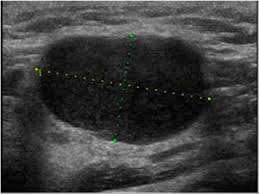

Diagnosis Of Papillary Thyroid Cancer from www.thyroidcancer.com The image may or may not suggest cancer, but definitive diagnosis requires removal of. Surgical levels of the neck. It can detect abnormal tissues, growths, and cysts and give a suspicion of cancer based on how those images look. This test will usually help determine that the nodule has a low chance of being cancerous (has characteristics of a benign nodule), or that it has some characteristics of a cancerous nodule, and therefore a biopsy is indicated. Level i constitutes lymph nodes above the anterior and posterior bellies of the digastric muscle cephalad to the hyoid bone and inferior to the inferior border of the mandible and includes the submental group of nodes. Thyroid nodules that are hypervascular, hypoechioc, or contain calcifications on ultrasound are more likely to be malignant. Ultrasound does not show the structures inside joints, dr. A neck ultrasound may help diagnose (find):

Physical examination/blood and urine tests. Surgical levels of the neck. Ultrasound and mapping of neck lymph nodes. Ultrasound is often one of the first line tests in the detection of cancer. Ultrasound does not show the structures inside joints, dr. Doctors often use ultrasound to guide a needle to do a biopsy (taking out fluid or small pieces of tissue to be looked at under a microscope). It can be used with a fine needle aspiration test or core biopsy test to accurately direct the tip of the needle into the lump. Before the node starts the lesions even very experienced specialist, the device will be able to register an increase, its contour irregularity, violation of the structure. The ultrasound technician (sonographer) may position your head to better access the side of your neck. Likewise, how do they test for thyroid cancer? A biopsy can be performed in cases where ultrasound cannot differentiate benign from malignant tumours. Keep in mind, however, that an ultrasound alone cannot make the diagnosis of cancer. Fna might also be used in patients whose cancer has been treated by surgery and/or radiation therapy, to help find out if a neck mass in the treated area is scar tissue or if it's a return (recurrence) of the cancer.

Ultrasoundis very sensitive and showsmany nodules that cannot be felt. In addition, the following tests may be used to diagnose head and neck cancer: Ultrasound does not show the structures inside joints, dr. Fna might also be used in patients whose cancer has been treated by surgery and/or radiation therapy, to help find out if a neck mass in the treated area is scar tissue or if it's a return (recurrence) of the cancer. Ultrasound technology cannot find ulcers, but other types of diagnostic tests can. Some research explores the potential for finding ulcers with an ultrasound, but experts do not have enough data to recommend it. The path report states loose fragments of poorly differentiated malignant epithelial cells with enlarged hyperchromatic irregular nuclei and apoptosis are seen in a hemorragic background that includes few scattered atypical keratinized squamous cells. Testing lymph nodes the lymph nodes in the neck are often the first place cancer cells spread to outside the primary site. Ultrasoundimaging is a noninvasive medical test that helps physicians diagnose and treat medical conditions. If this lump is of concern then a biopsy would be the next step. Cancer of the liver or fatty. Optimal positioning and exposure of the neck for ultrasound of the thyroid and parathyroid glands (a, b) and lateral neck for lymph node examination and mapping (c).while the vast majority of patients are supine on the exam table with a pillow supporting the shoulders to allow gentle neck extension, keep in mind that some patients have beautiful anatomy (d) that allows ultrasound exam even in. Abnormal enlargement of the spleen.

Confirming that a lump in the neck is developing from the thyroid or connected tissue. The sonographer then gently presses the transducer against the side of your neck. Identification of a suspicious lymph node increases the likelihood of cancer and may warrant fna of the node in lieu of the thyroid (see fig. Surgical levels of the neck. This test will usually help determine that the nodule has a low chance of being cancerous (has characteristics of a benign nodule), or that it has some characteristics of a cancerous nodule, and therefore a biopsy is indicated. The ultrasound technician (sonographer) may position your head to better access the side of your neck. During a physical examination, the doctor feels for any lumps on the neck, lips, gums, and cheeks. Abnormal enlargement of the spleen. In my experience an ultrasound won't tell you if you have cancer, it just shows a lump. If cancer is found in a lymph node, you may need a neck dissection or other additional treatment. Doctors often use ultrasound to guide a needle to do a biopsy (taking out fluid or small pieces of tissue to be looked at under a microscope). Throat cancer is often easily seen by an ent exam. It can detect abnormal tissues, growths, and cysts and give a suspicion of cancer based on how those images look.